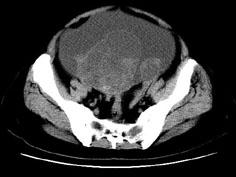

问题 女,27岁,腹胀伴消瘦两个月,CT检查如图所示,应诊断为 ( )

选项 A、卵巢粘液性囊腺瘤 B、卵巢粘液性囊腺癌 C、卵巢浆液性囊腺瘤 D、卵巢浆液性囊腺癌 E、子宫肌瘤

答案 D